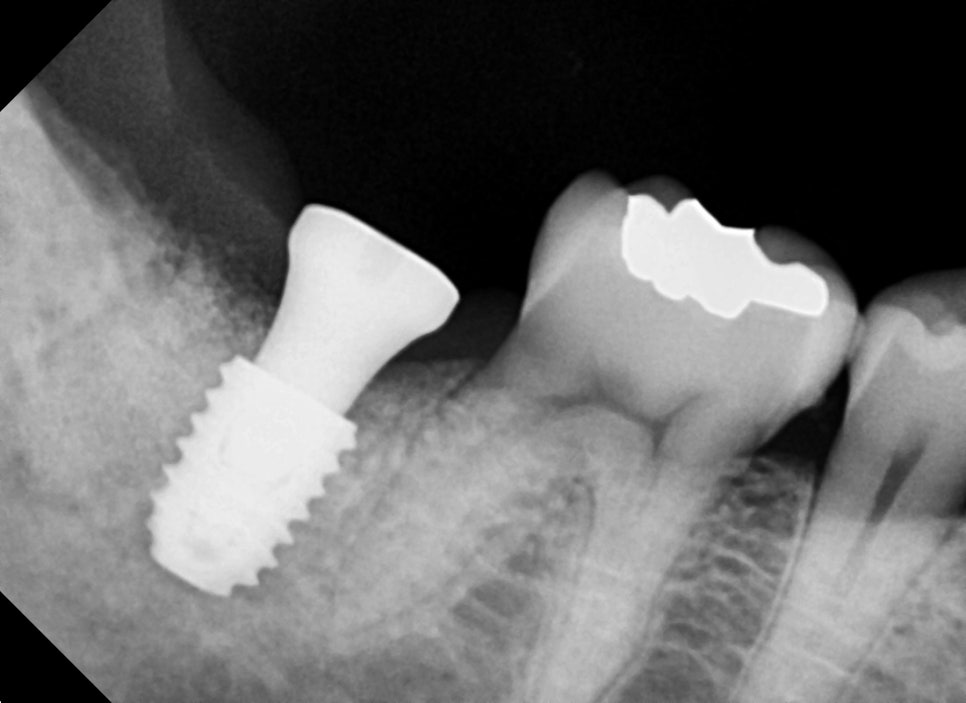

발치 후 바로 임플란트 수술과 동시에 치조골 이식술을 진행합니다.

다행히 초기 고정이 좋았기 때문에

추후 보철을 위한 2차 수술까지 한번에 하면서

치아의 원심쪽 뿌리 공간에 다량의 치조골 이식술을 진행했습니다.

2달 후 사진입니다.

치조골 이식술을 한곳이 의도한 바와 같이 아주 잘 아물었습니다.

치유도 좋고 임플란트의 고정 성도 좋아서 바로 보철 단계를 진행했습니다.